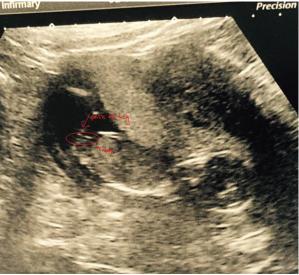

Hi I have been getting mixed guesses and would just like to know what you all think this is my 14 week scan. Thanks x

Could see that going either way from this shot, sorry xx

Boy :) There is stacking there.

this might help alot of people think the shadow above the leg is part of the nub its not its part of the leg. someone told me to change contrast and also editing and you would be able to tell if it part of it and its not.Attachment 25884

I'm pretty sure that is part of the nub. Were you hoping for a girl?

Leaning girl

Girly IMO.

You could well be right that the bump isn't part of the nub, so I will give you a slight girly lean now.